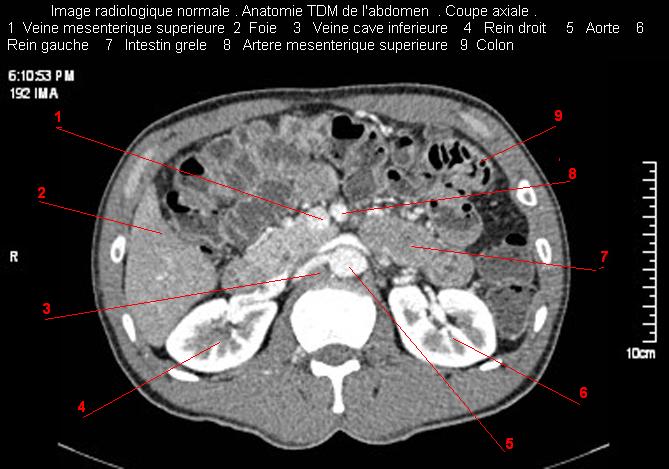

Images radiologique TDM normale de abdomen et tube digestif en coupe axiale ( CT scanner )  :

Coupe axiale     Coupe frontale      Coupe  sagitale